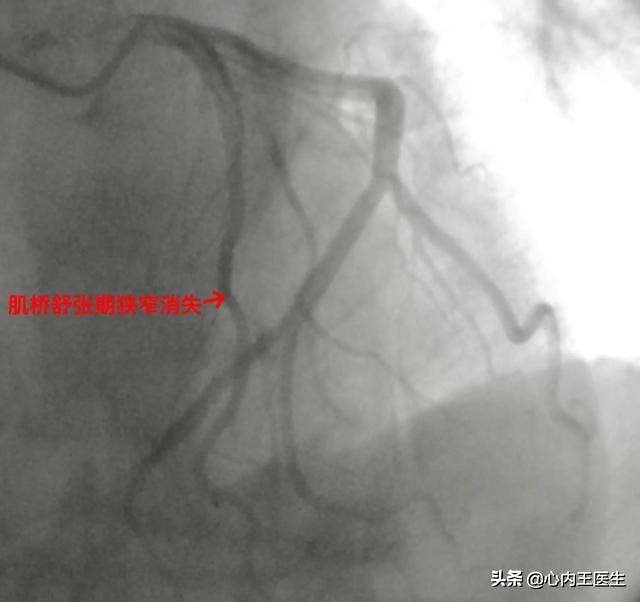

今天上午,这位大爷行冠状动脉造影提示冠状动脉肌桥,这就很明确的排除了冠心病。肌桥一般问题不大,就是血管在部分肌肉的下面穿过,可能活动状态下影响部分血供,心脏肌肉收缩的时候血管被压迫变窄,舒张期狭窄明显解除。